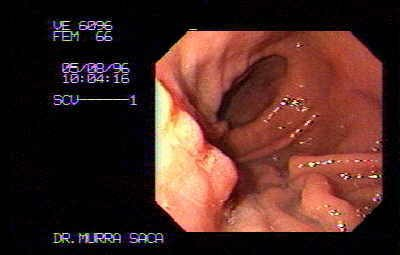

Paciente Masculino de 51 Años:

Hermano de prestigioso Cirujano Pediatra de El Salvador. El cual me solicita que le practique este estudio, le diagnosticamos este carcinoma obstructivo, la imagen endoscópica de control, Fue después de un año de habérsele diagnosticado por lo que Se le había practicado una derivación en omhmeda por haber sido irresecable al intento quirúrgico es de notar que esta imagen endoscópica es después de haber recibido quimioterapia y radiaciones con Cobalto.